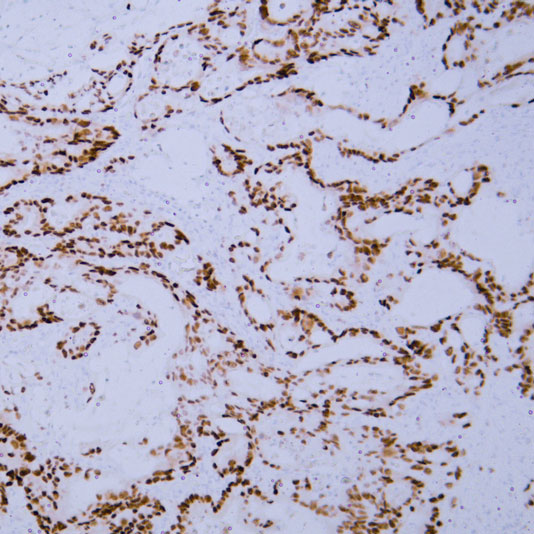

2 Staining of paraffin-embedded breast cancer tissue sections: Mammaglobin staining is positive, but section detachment occurs due to insufficient baking time.

Typical Example:CD34 staining of paraffin-embedded human placental tissue sections:

HRP-directly labeled secondary antibody: Weak positive staining with low background;

Polymer enzyme-labeled secondary antibody: Strong positive staining with clean background and distinct contrast.

Conclusion: Different chromogenic systems yield distinct chromogenic results. Polymer enzyme-labeled secondary antibodies demonstrate higher sensitivity, cleaner background, and more distinct contrast compared to conventional HRP-directly labeled secondary antibodies.